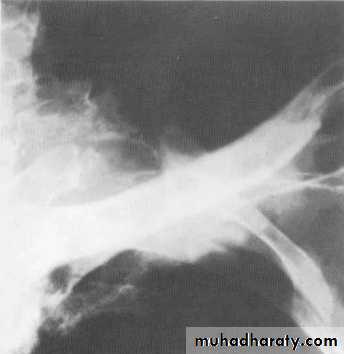

Tuberculoma